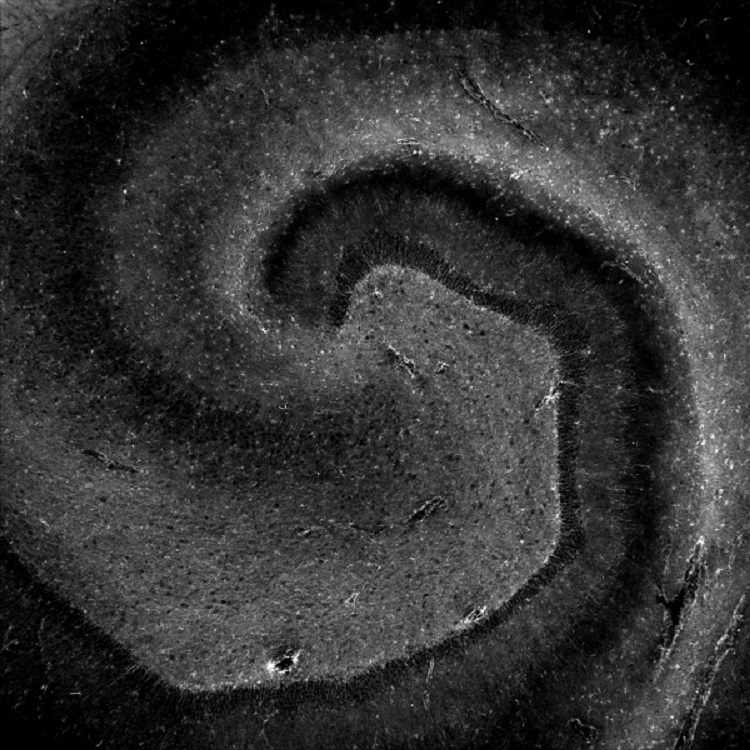

Microscopic photo capturing cells within the hippocampus,

This microscopic photo captures cells within a brain region, the hippocampus, involved with learning and memory. Every lived experience that we are able to remember has boosted the formation of new connections in our brains. These connections are affected in diseases that impair memory, such as Alzheimer's disease. (Art of Research photo by Natalia de Menezes Lyra e Silva)